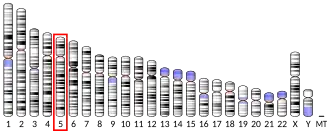

| Aliases | SLC26A2, D5S1708, DTD, DTDST, EDM4, MST153, MSTP157, solute carrier family 26 member 2 | ||||||||||||||||||||||||||||||||||||||||||||||||||

| External IDs | OMIM: 606718; MGI: 892977; HomoloGene: 73876; GeneCards: SLC26A2; OMA:SLC26A2 - orthologs | ||||||||||||||||||||||||||||||||||||||||||||||||||